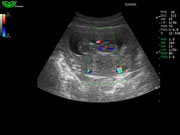

Отображение гармоники ткани (THI)

Не только улучшает пространственное разрешение, но и значительно повышает контраст изображения. Специально для полных пациентов, чтобы врач более точно ставил диагноз.

- Улучшает пространственное и контрастное разрешение изображения.

- Доступно для всех датчиков.

- Возможность выбора до 5 полос частот.

Оптимизация изображения (I-image)

- Снижает зернистость и устраняет помехи изображения.

- Улучшает гладкость изображения, при этом улучшает четкость очертаний определенных структур.